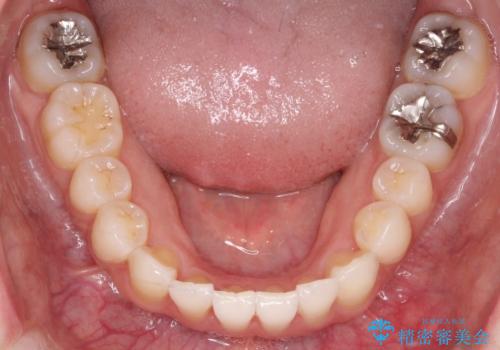

【インビザライン】前歯の凸凹をなおしたい

- 前歯の凸凹を主訴に来院されました。

上顎の急速拡大を行なったのちインビザラインにて治療を行なっております。

今回のケースは後戻りのリスクを低くし、またディスキング量を減らすために上顎の急速拡大を行なっております。